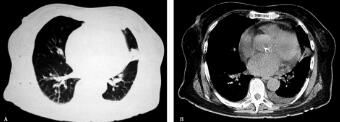

10.胸部CT(2012年6月20日):两肺支气管血管纹理束增多、紊乱;左肺上叶多发斑片状渗出影及索条影,左侧胸腔见条带形液性密度影;心脏影增大,心包少量积液(图1A肺窗、B纵隔窗)。

图1

首先根据化验检查结果:①末梢血白细胞计数和中性粒细胞百分比均增高;②胸部影像学示双肺多发小片渗出影。结合患者的病史和体格检查结果,首先考虑为感染性发热,引起发热的原因为社区获得性肺炎(community acquired pneumonia,CAP)。由于病原学尚不清楚,需要给予经验性抗感染治疗,观察病情的同时继续查找其他感染灶。关于体检发现主动脉瓣第二听诊区、二尖瓣听诊区1/6级收缩期吹风样杂音,入院时即考虑感染性心内膜炎可能,因为经胸壁心脏彩超(TTE)未见瓣膜赘生物,于是想当然地除外了感染性心内膜炎。双下肢血管超声未见血栓,肺栓塞临床评估低度可能,无急诊行CT肺动脉造影指征。D-二聚体升高考虑与感染和发热相关。

评价:初步诊断“社区获得性肺炎(左侧)、反应性胸膜炎、低氧血症”明确,然而单纯应用社区获得性肺炎能够完全解释患者的临床症状——发热吗?显然存在以下疑问:患者胸部CT影像学炎症程度和白细胞升高程度均为轻度,而血沉和C-反应蛋白以及D-二聚体均明显升高,二者不匹配。